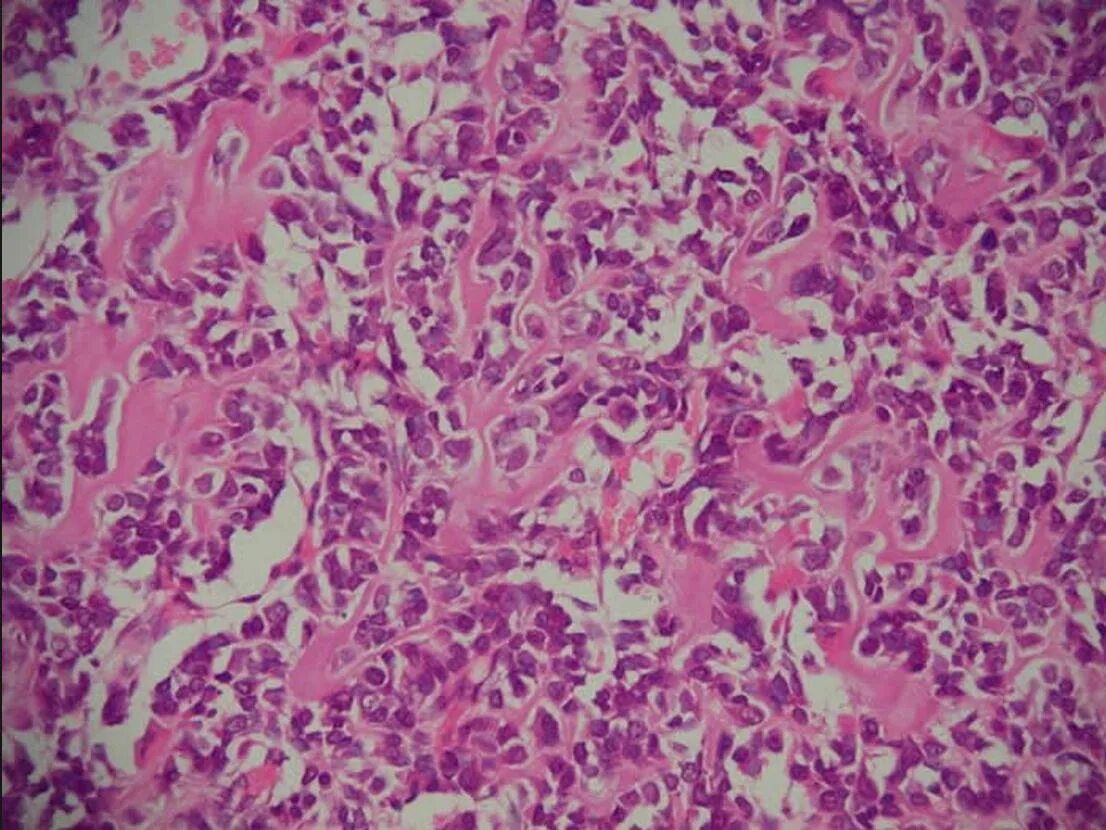

Патан пф